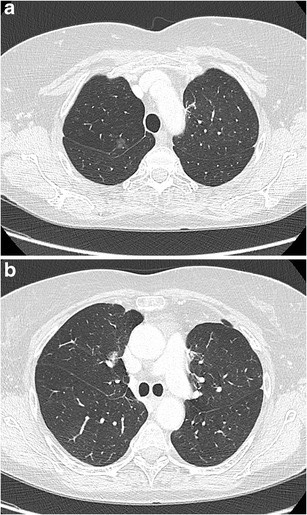

2993. Учитывая локализацию очагов бронхиолоальвеолярного рака в лёгком по данным томографических срезов

пациенту показано выполнение ________ с медиастинальной лимфодиссекцией